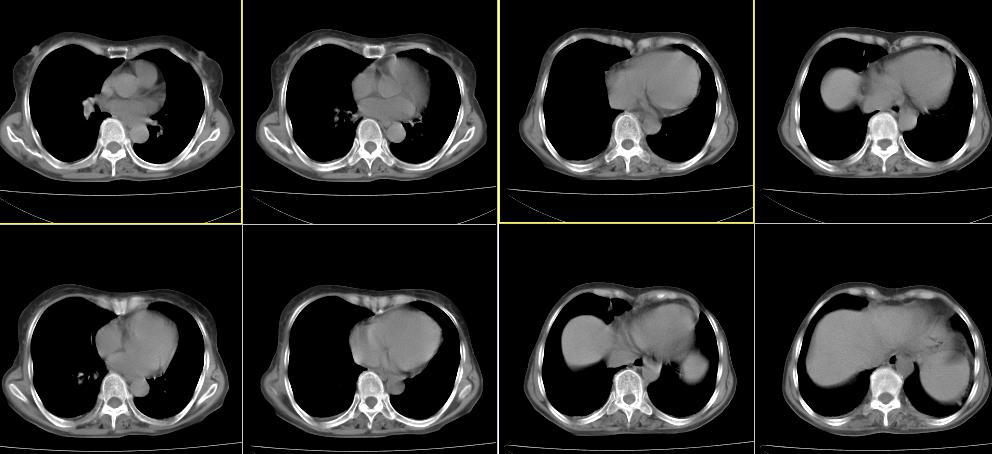

标题: CT26857:女,60岁,胃部不适前来就诊,不咳嗽,乏力,胸椎 [打印本页]

1、胸椎有骨质破坏伴周软组织,考虑胸椎转移。2、考虑左肺上叶尖后段支气管开口区周围型肺癌可能。

1、胸椎有骨质破坏伴周软组织,考虑胸椎转移。2、考虑左肺上叶尖后段支气管开口区周围型肺癌可能。建议行纤支镜检查!

1、胸椎有骨质破坏伴周软组织,考虑胸椎转移。2、考虑左肺中央型肺癌可能。

支持中央型肺癌,胸椎转移。

1)考虑左肺中央型肺癌。2)胸椎转移瘤不排除;建议行mri检查。